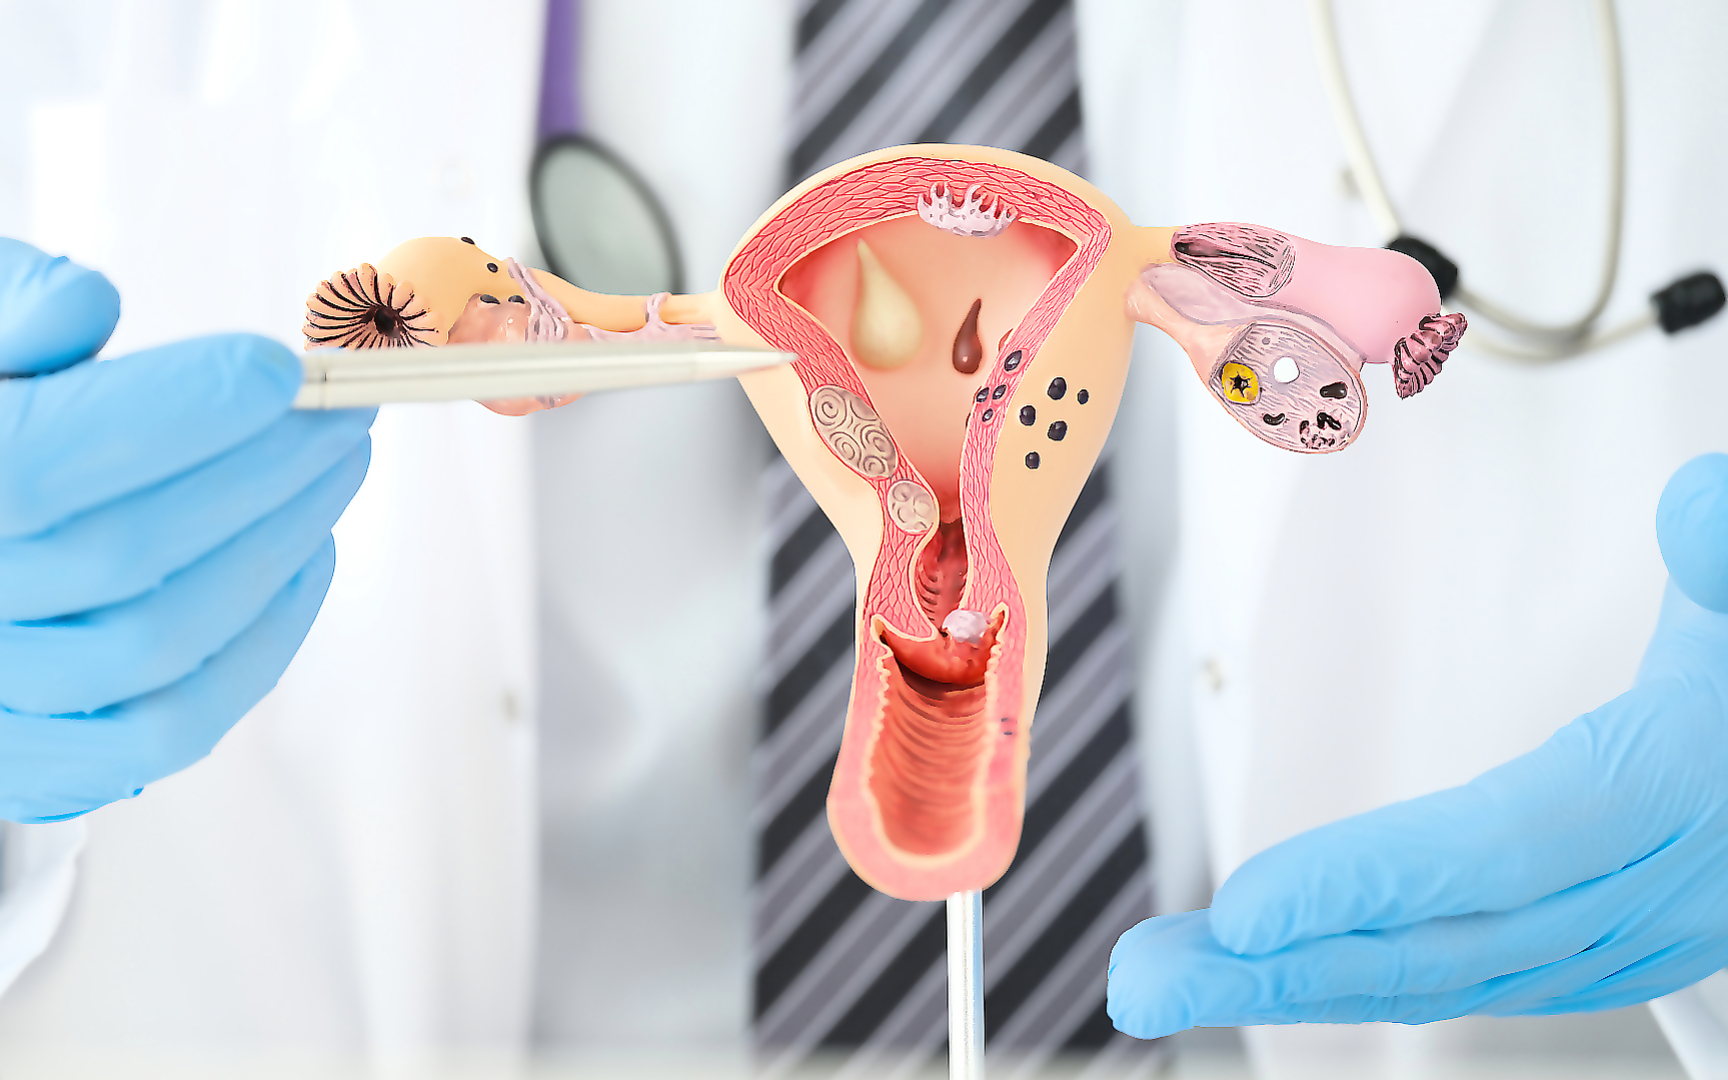

Анатомия женского организма: строение и функции матки

Раздел: Фотопуть к знанию